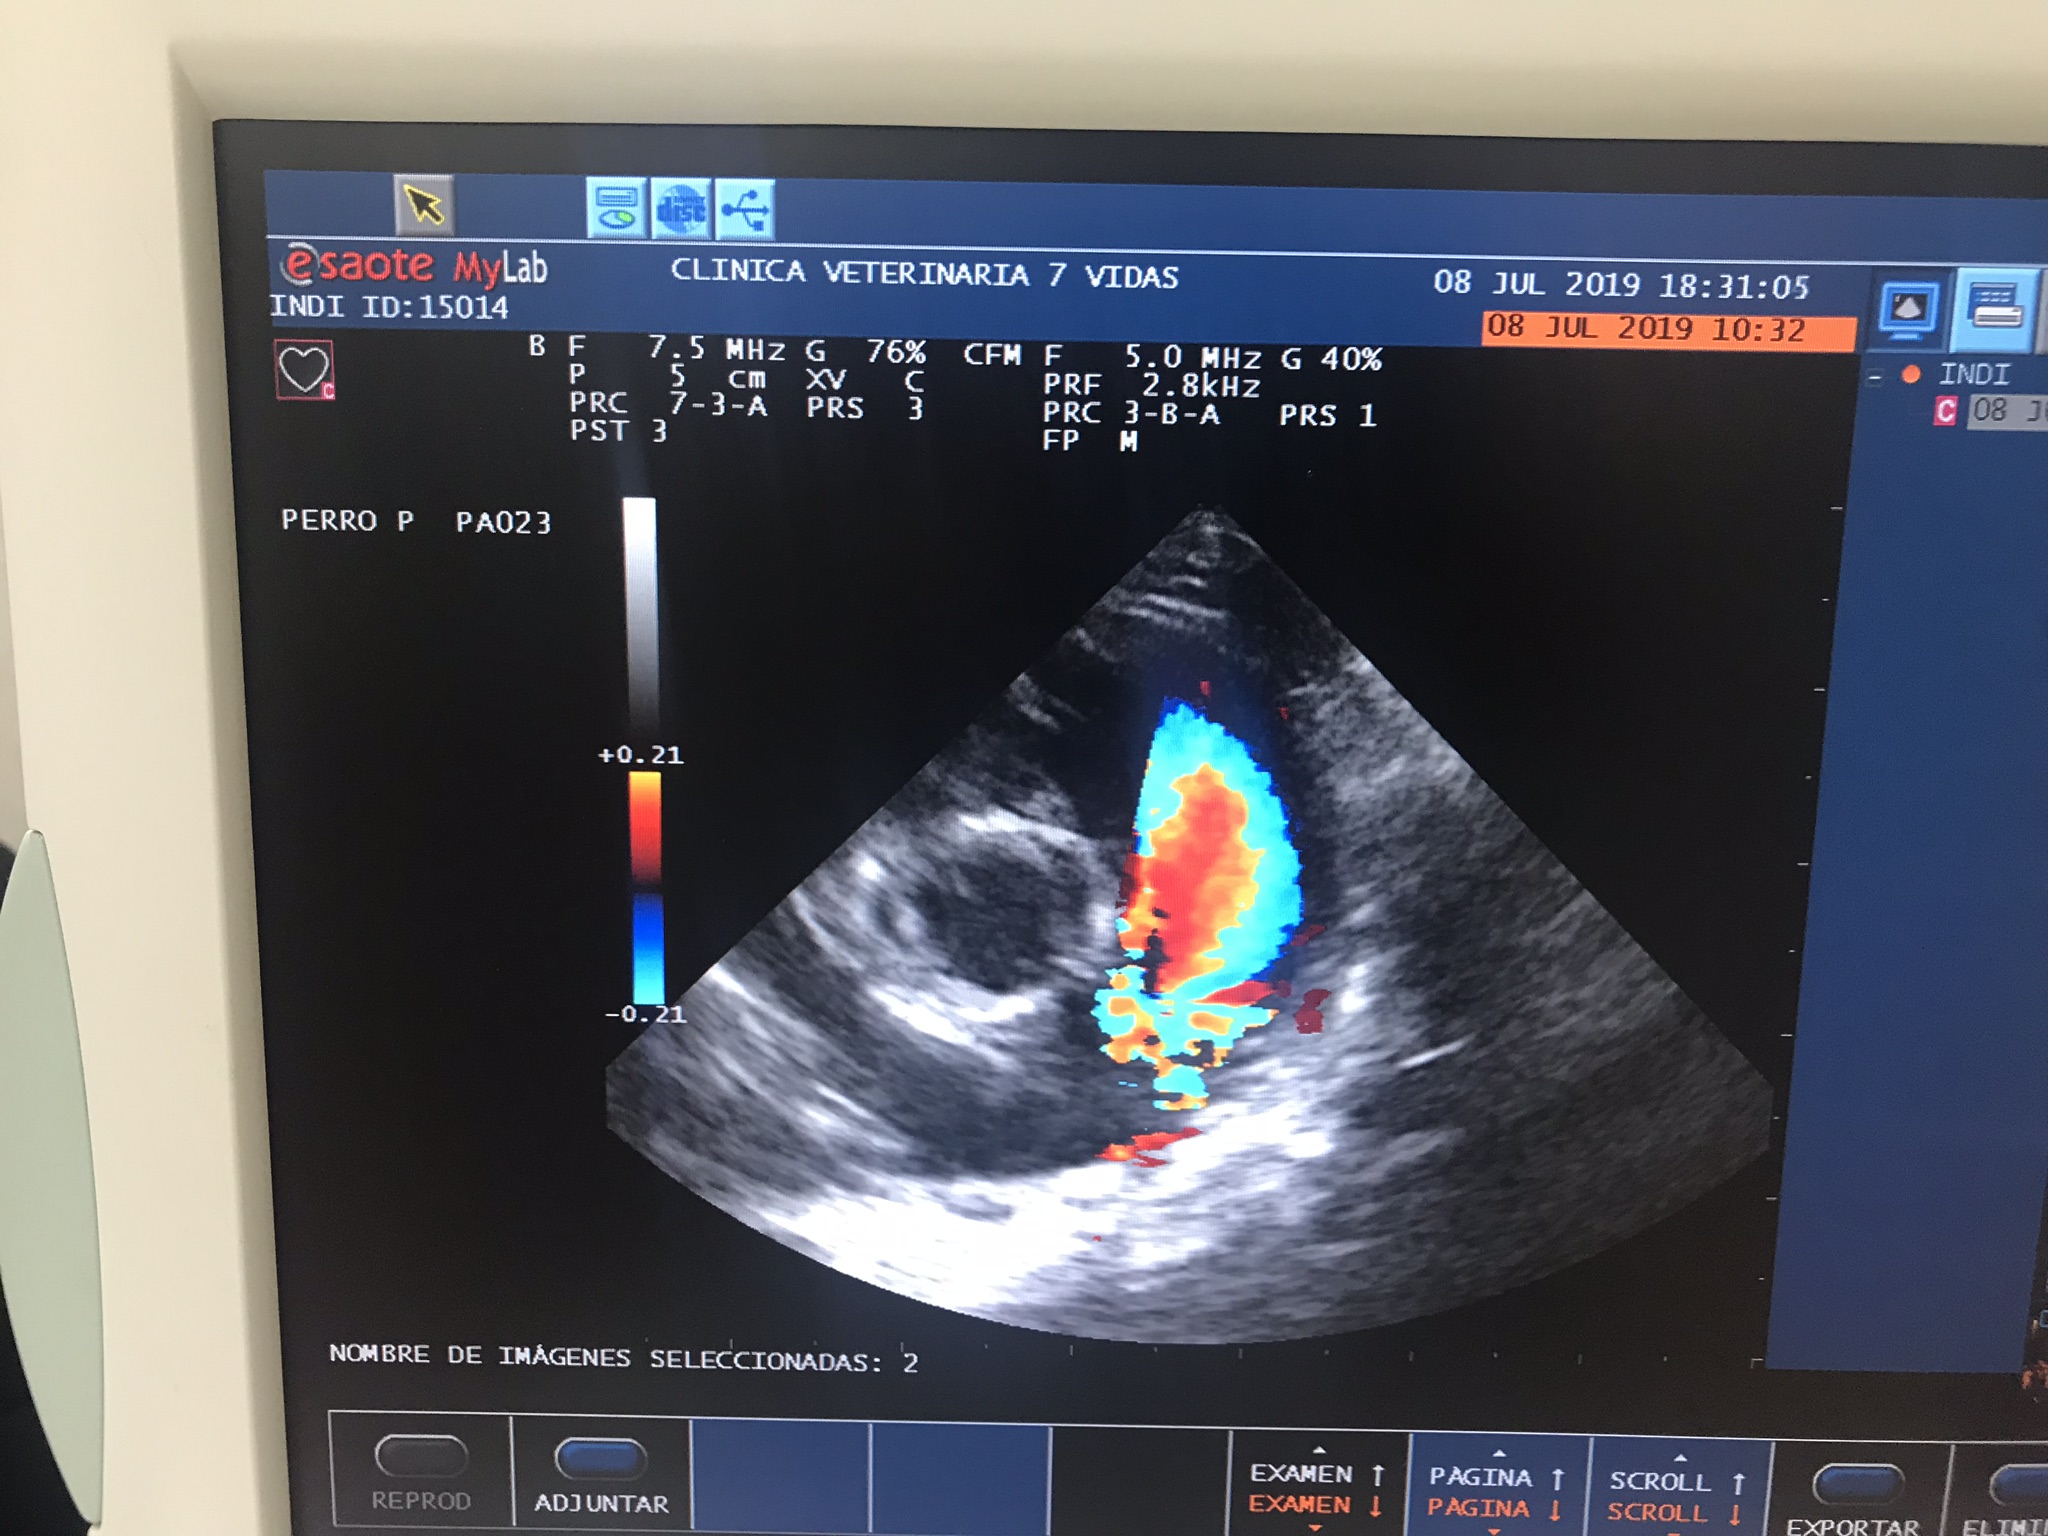

- Cardiología

Centro Veterinario Los Ángeles-7Vidas se especializa en el cuidado de una amplia gama de animales, incluyendo especies exóticas, aves y casos de cardiología y oftalmología. Este centro veterinario ofrece servicios completos para el bienestar de varios tipos de animales, asegurándose de que reciban la atención especializada que necesitan.